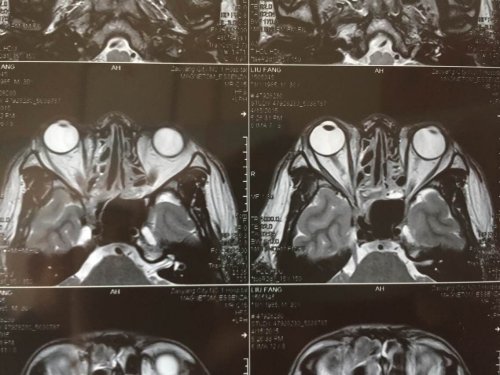

昨日(2015—04—15)MR影像报告:

03—27 影像图:

04—15 影像图

03—27 影像图:

04—15 影像图